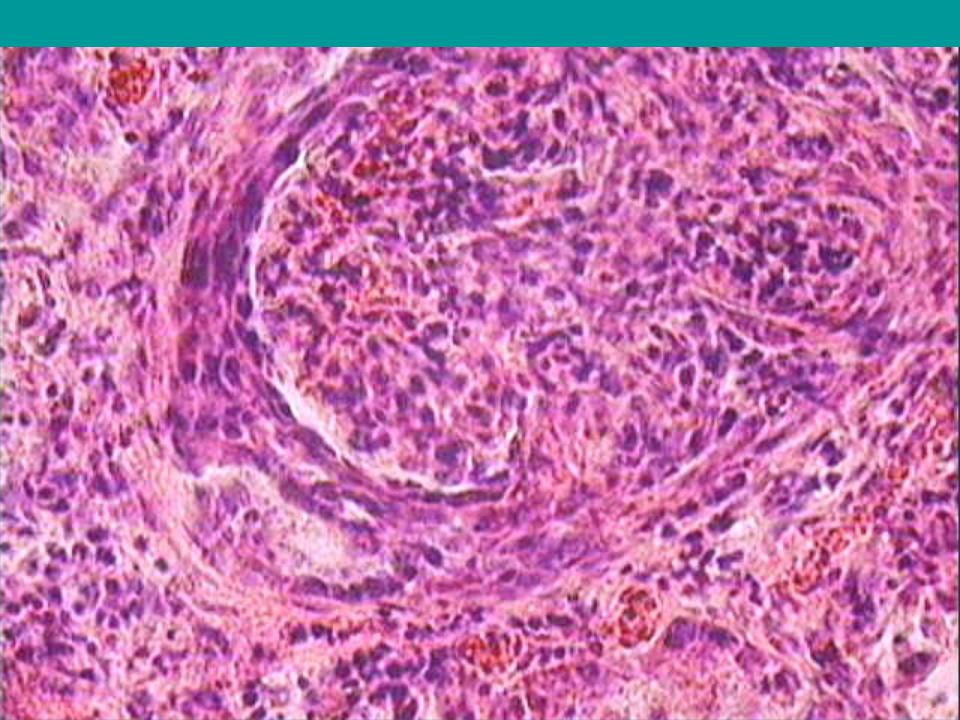

Механизм остро го диффузного гломерулонефрита